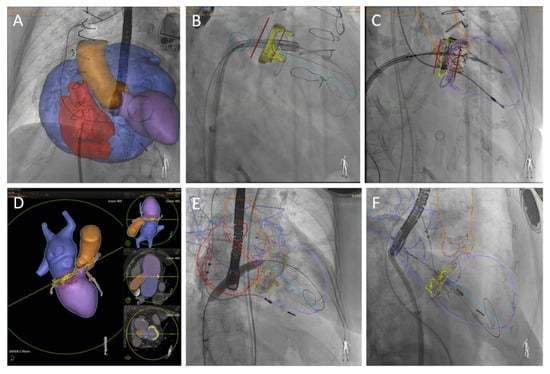

Degenerative mitral stenosis (MS) secondary to extensive mitral annular calcification (MAC) represents a growing clinical challenge in an aging population. These patients are often elderly, frail, and harbor a significant burden of comorbidities, rendering conventional mitral valve surgery prohibitively high-risk. While transcatheter mitral [...] Read more.

Degenerative mitral stenosis (MS) secondary to extensive mitral annular calcification (MAC) represents a growing clinical challenge in an aging population. These patients are often elderly, frail, and harbor a significant burden of comorbidities, rendering conventional mitral valve surgery prohibitively high-risk. While transcatheter mitral valve replacement (TMVR) has emerged as a potential alternative, the current evidence is only derived from single-arm observational registries. Therefore, the transition toward randomized controlled trials to define optimal patient selection and long-term prosthetic durability is necessary. This review examines the current landscape of TMVR for degenerative MS, focusing on the role of multimodal pre-procedural planning, procedural technique, and prevention of the principal complications. The integration of echocardiography and multi-slice computed tomography (MSCT) is essential for evaluating anatomical feasibility, particularly in predicting neo left ventricle outflow tract (neo-LVOT) obstruction, the primary determinant of procedural mortality. However, it is limited due to the absence of standardized protocol. We are showing the outcomes of off-label balloon-expandable aortic prostheses and dedicated TMVR system, which are the only two devices which data in patients with MS are available. Despite high technical success rates in specialized centers, complications, including paravalvular leak, valve thrombosis, and device migration, remain more prevalent than in aortic interventions. We present some tips and tricks to prevent and manage adverse events. TMVR represents a transformative frontier for inoperable patients with severe MAC. However, its routine clinical adoption requires further refinement of dedicated technologies and standardized imaging protocols to improve safety and bridge the gap between palliative medical therapy and definitive intervention. Full article

Show Figures

Figure 1